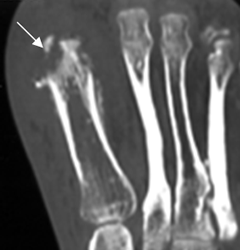

Fig 30. Osteomielitis.

TAC reconstrucción coronal. Edema de tejidos blandos rodeando el hallux, con osteolisis en la parte distal del metatarsiano, por osteomielitis.